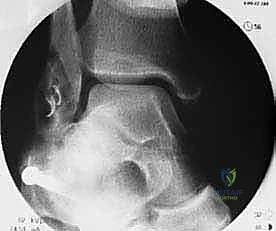

إعادة بناء الأربطة باستخدام الطعوم (Allograft): تقنية جراحية متقدمة

في الماضي، كانت العمليات تقتصر على محاولة خياطة الأربطة الممزقة (عملية Broström). ولكن في حالات عدم الاستقرار المزمن، تكون الأنسجة الأصلية قد تآكلت وضعفت لدرجة لا تسمح بخياطتها بنجاح. لذلك، يعتمد الأستاذ الدكتور محمد هطيف على تقنية إعادة البناء باستخدام الطعوم.

ما هو الطعم (Allograft)؟

هو نسيج وتري أو ليّفي يتم الحصول عليه من بنك الأنسجة (متبرع). الميزة الكبرى لاستخدام الـ Allograft هي أن المريض لا يضطر للتضحية بأي من أوتاره السليمة (كما يحدث في الـ Autograft)، مما يقلل من الألم الجراحي، يسرع من عملية الشفاء، ويمنع حدوث أي ضعف في أجزاء أخرى من الساق.

2. التقييم بالمنظار (Arthroscopy) بتقنية 4K:

قبل البدء في إعادة البناء، يقوم الدكتور هطيف بإدخال كاميرا دقيقة جداً (منظار) داخل مفصل الكاحل. تتيح شاشات الـ 4K رؤية تفاصيل المفصل بوضوح مذهل. يتم في هذه الخطوة تنظيف المفصل من أي أنسجة ملتهبة، إزالة الشظايا العظمية أو الغضروفية السائبة، ومعالجة أي تلف في الغضروف ناتج عن عدم الاستقرار المزمن.

4. حفر الأنفاق العظمية:

باستخدام أدوات جراحية دقيقة، يقوم الدكتور هطيف بعمل أنفاق صغيرة جداً في عظم الشظية (Fibula) وعظم الكاحل (Talus) وعظم العقب (Calcaneus). تعتمد هذه الخطوة على المعرفة التشريحية العميقة لضمان وضع الأربطة الجديدة في مسارها التشريحي الطبيعي (Anatomical Reconstruction).

5. تثبيت الطعم:

يتم تمرير الطعم داخل الأنفاق العظمية وتثبيته بقوة باستخدام براغي تداخلية (Interference screws) مصنوعة من مواد تذوب حيوياً وتندمج مع العظم بمرور الوقت. يتم ضبط شد الطعم بدقة لضمان ثبات الكاحل مع الحفاظ على نطاق الحركة الطبيعي.